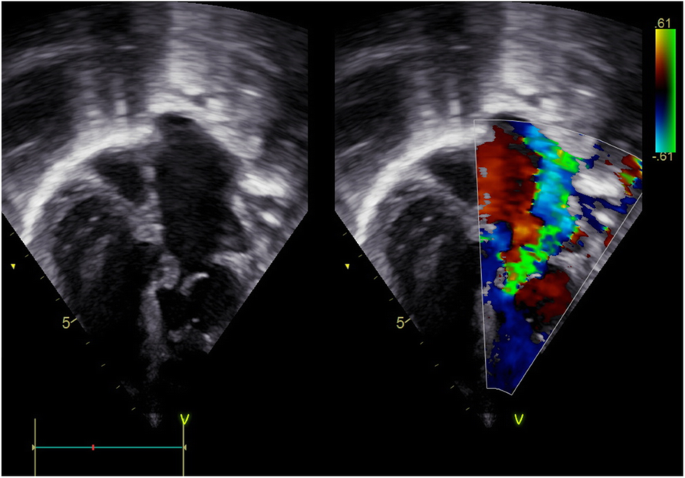

A 3 year- old female, a known patient with ccTGA was brought back to the clinic with new onset complaints of exercise intolerance, profuse sweating. She had a diagnosis of ccTGA at the age of 1 year. She had been symptomatically controlled on frusemide and captopril. Her clinical examination revealed a sick child, who was diaphoretic, with weight, height and SPO2 of 10 kg, 87 cm and 96% respectively. She had a soft first heart sound at the apex, the P2 component of second heart sound was accentuated, with a pan systolic murmur at the apex radiating to the axilla and back. Her TTE showed ccTGA with a large non-restrictive inlet VSD of 18 mm in diameter. There was a new onset severe tricuspid valve regurgitation, moderate pulmonary valve regurgitation and mild mitral valve regurgitation (Fig. 4). Her ECG revealed: junctional tachycardia. The ventricular rate was 136 bpm with RS in leads V5 and V6. There were retrograde P waves embedded in the T wave causing notching of the T waves (ECG Figure 3).